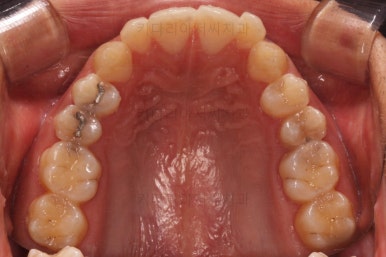

초진 시 입안의 모습입니다.

앞니가 약간 삐뚠 것 말고는 큰 문제는 없어보이네요.

교합이나 가지런한 느낌 매우 좋아졌고요.

특히 옆 라인에서도 둥글었던 윗입술도 오목한 곡선이 생기면서 돌출감이 좋아졌고 턱끝의 윤곽도 생기면서 무턱 느낌도 좋아졌습니다.

윗니의 위치를 보면 처음은 아랫입술에 가려질 정도로 아래로 내려와 있었는데 치료 후에는 앞니가 보이는 정도로 위치 조절이 잘 되었네요.